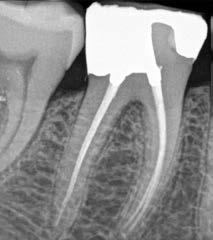

6. a–d. ábrák: A bal alsó második nagyőrlőfogon (3.7) kialakított konzervatív hozzáférési nyíláson keresztül végzett endodonciai kezelés lépései. A mezialis gyökér jelentős mértékben görbült. A gyökértömés hidraulikus kondenzációs technikával készült.

b. ábrák: A jobb alsó első nagyőrlőfogon (4.6) lévő cirkóniumkoronán keresztül elvégzett endodonciai kezelés. A hozzáférési nyílás kialakítása a lehető legkonzervatívabb módon történt. A gyökértömés hidraulikus kondenzációs technikával készült.

egyszerű obturációs technika, az anyag viszkozitási tulajdonságai és a pulpakamra viszonylag egyszerű tisztíthatósága a kezelésünk prognózisának veszélyeztetése nélkül teszi lehetővé az endodonciai beavatkozások lehető legkonzervatívabb módon történő kivitelezését. A bemutatott esetek ellátása során az Aurum Blue rendszert (Meta Biomed) használtuk a gyökércsatornák megmunkálására, míg a gyökértömés elkészítése során hideg hidraulikus kondenzációs technikát alkalmaztunk a kalcium-szilikát alapú CeraSeal (Meta Biomed) sealer felhasználásával (8. ábra).